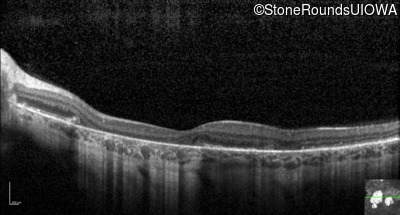

Optical Coherence Tomography - Left - 20/60 +2 sc

Exemplar / OCT Stack